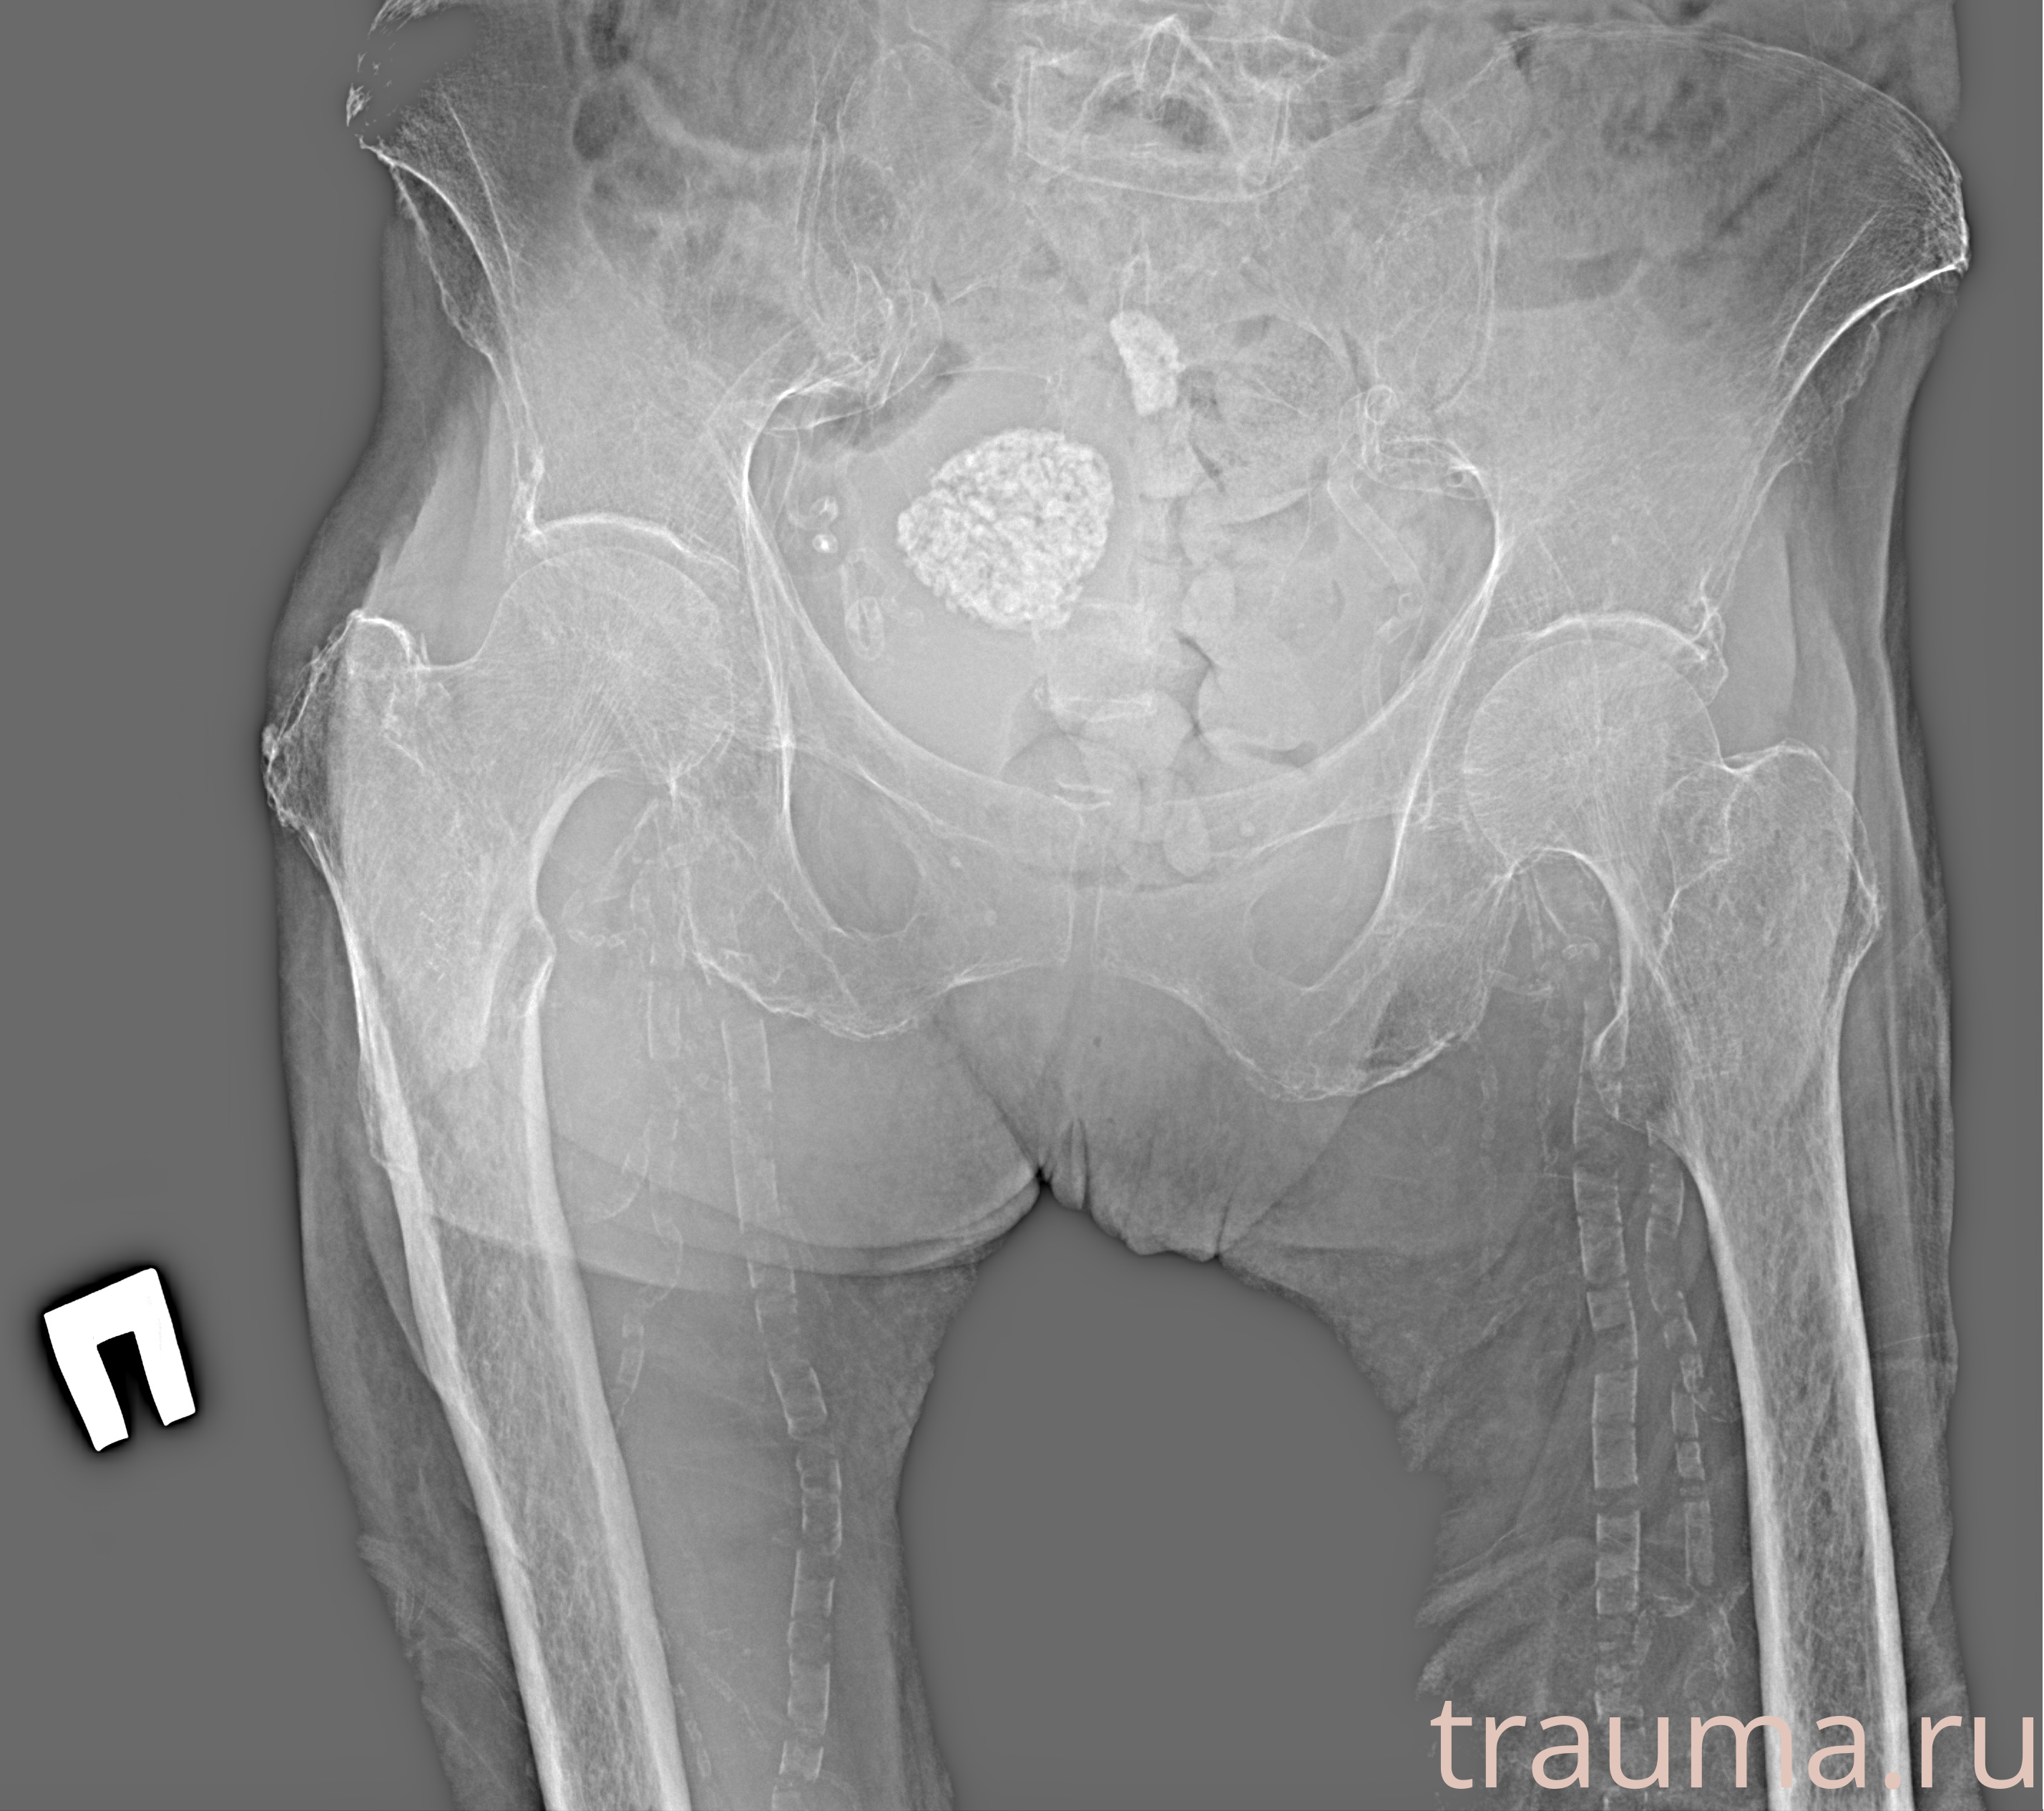

Рентгенограммы

Рентген на дому: по вашему адресу приезжает врач-рентгенолог, травматолог-ортопед с мобильным рентгеновским аппаратом, проводит диагностику травмы или заболевания, делает необходимые рентгенограммы, дает рекомендации по дальнейшему лечению. Получить качественные снимки в домашних условиях возможно благодаря уникальной методике, разработанной МосРентген Центром для института  Склифосовского